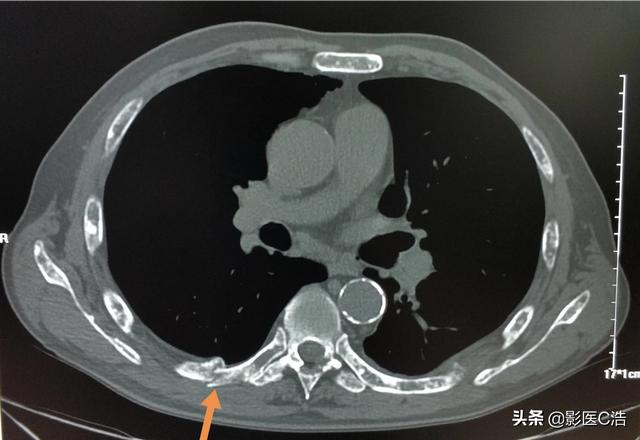

Il y a quelques jours, un patient atteint d'un cancer du poumon avec métastases osseuses a été diagnostiqué. Ses symptômes sont des douleurs lombaires de longue durée, ils ont toujours pensé qu'il s'agissait d'un claquage musculaire lombaire ou d'une hernie discale lombaire, mais ils ne se sont pas inquiétés, la douleur est vraiment sérieuse et les symptômes nerveux des membres inférieurs sont apparus. ...... recherche détaillée des antécédents médicaux, découverte que le patient présente depuis longtemps des symptômes de toux, ce qui permet de soupçonner un cancer du poumon avec métastases osseuses, l'examen tomodensitométrique du poumon a révélé que le foyer principal ...... est un énorme cancer du poumon.

en effetLe diagnostic d'une maladie comme les métastases osseuses est difficile pour le cœur du médecincar une fois les métastases osseuses apparues.Cela signifie que le cancer est à un stade avancé.Les chances de survie du patient peuvent être considérablement réduites et la durée de survie raccourcie. Qu'est-ce qu'une métastase osseuse ? Pourquoi certains patients atteints de cancer ont-ils déjà des métastases osseuses lorsqu'on les découvre ? Quelles sont les caractéristiques des symptômes douloureux chez les patients atteints de métastases osseuses ? Discutons-en ensemble.

Un homme de 46 ans a été vu en consultation pour une douleur persistante dans le bas du dos. On pensait que cette douleur était due à une hernie discale. Une radiographie a été effectuée et n'a révélé aucune anomalie. Les métastases osseuses provoquant une légère destruction osseuse sont invisibles à la radiographie, de même qu'une hernie discale. Je n'ai donc pas particulièrement pensé à la possibilité d'une métastase. Une semaine plus tard, comme il n'y avait toujours pas d'amélioration, il est venu passer un scanner et a découvert qu'une vertèbre lombaire avait été rongée. En voyant une telle image, le médecin spécialiste de l'imagerie a dû penser à la possibilité de métastases et a suggéré au patient de passer un scanner du thorax, et effectivement, il y avait une masse dans les poumons, qui a été considérée comme une métastase osseuse d'un cancer du poumon, ce qui a été confirmé par la pathologie plus tard.